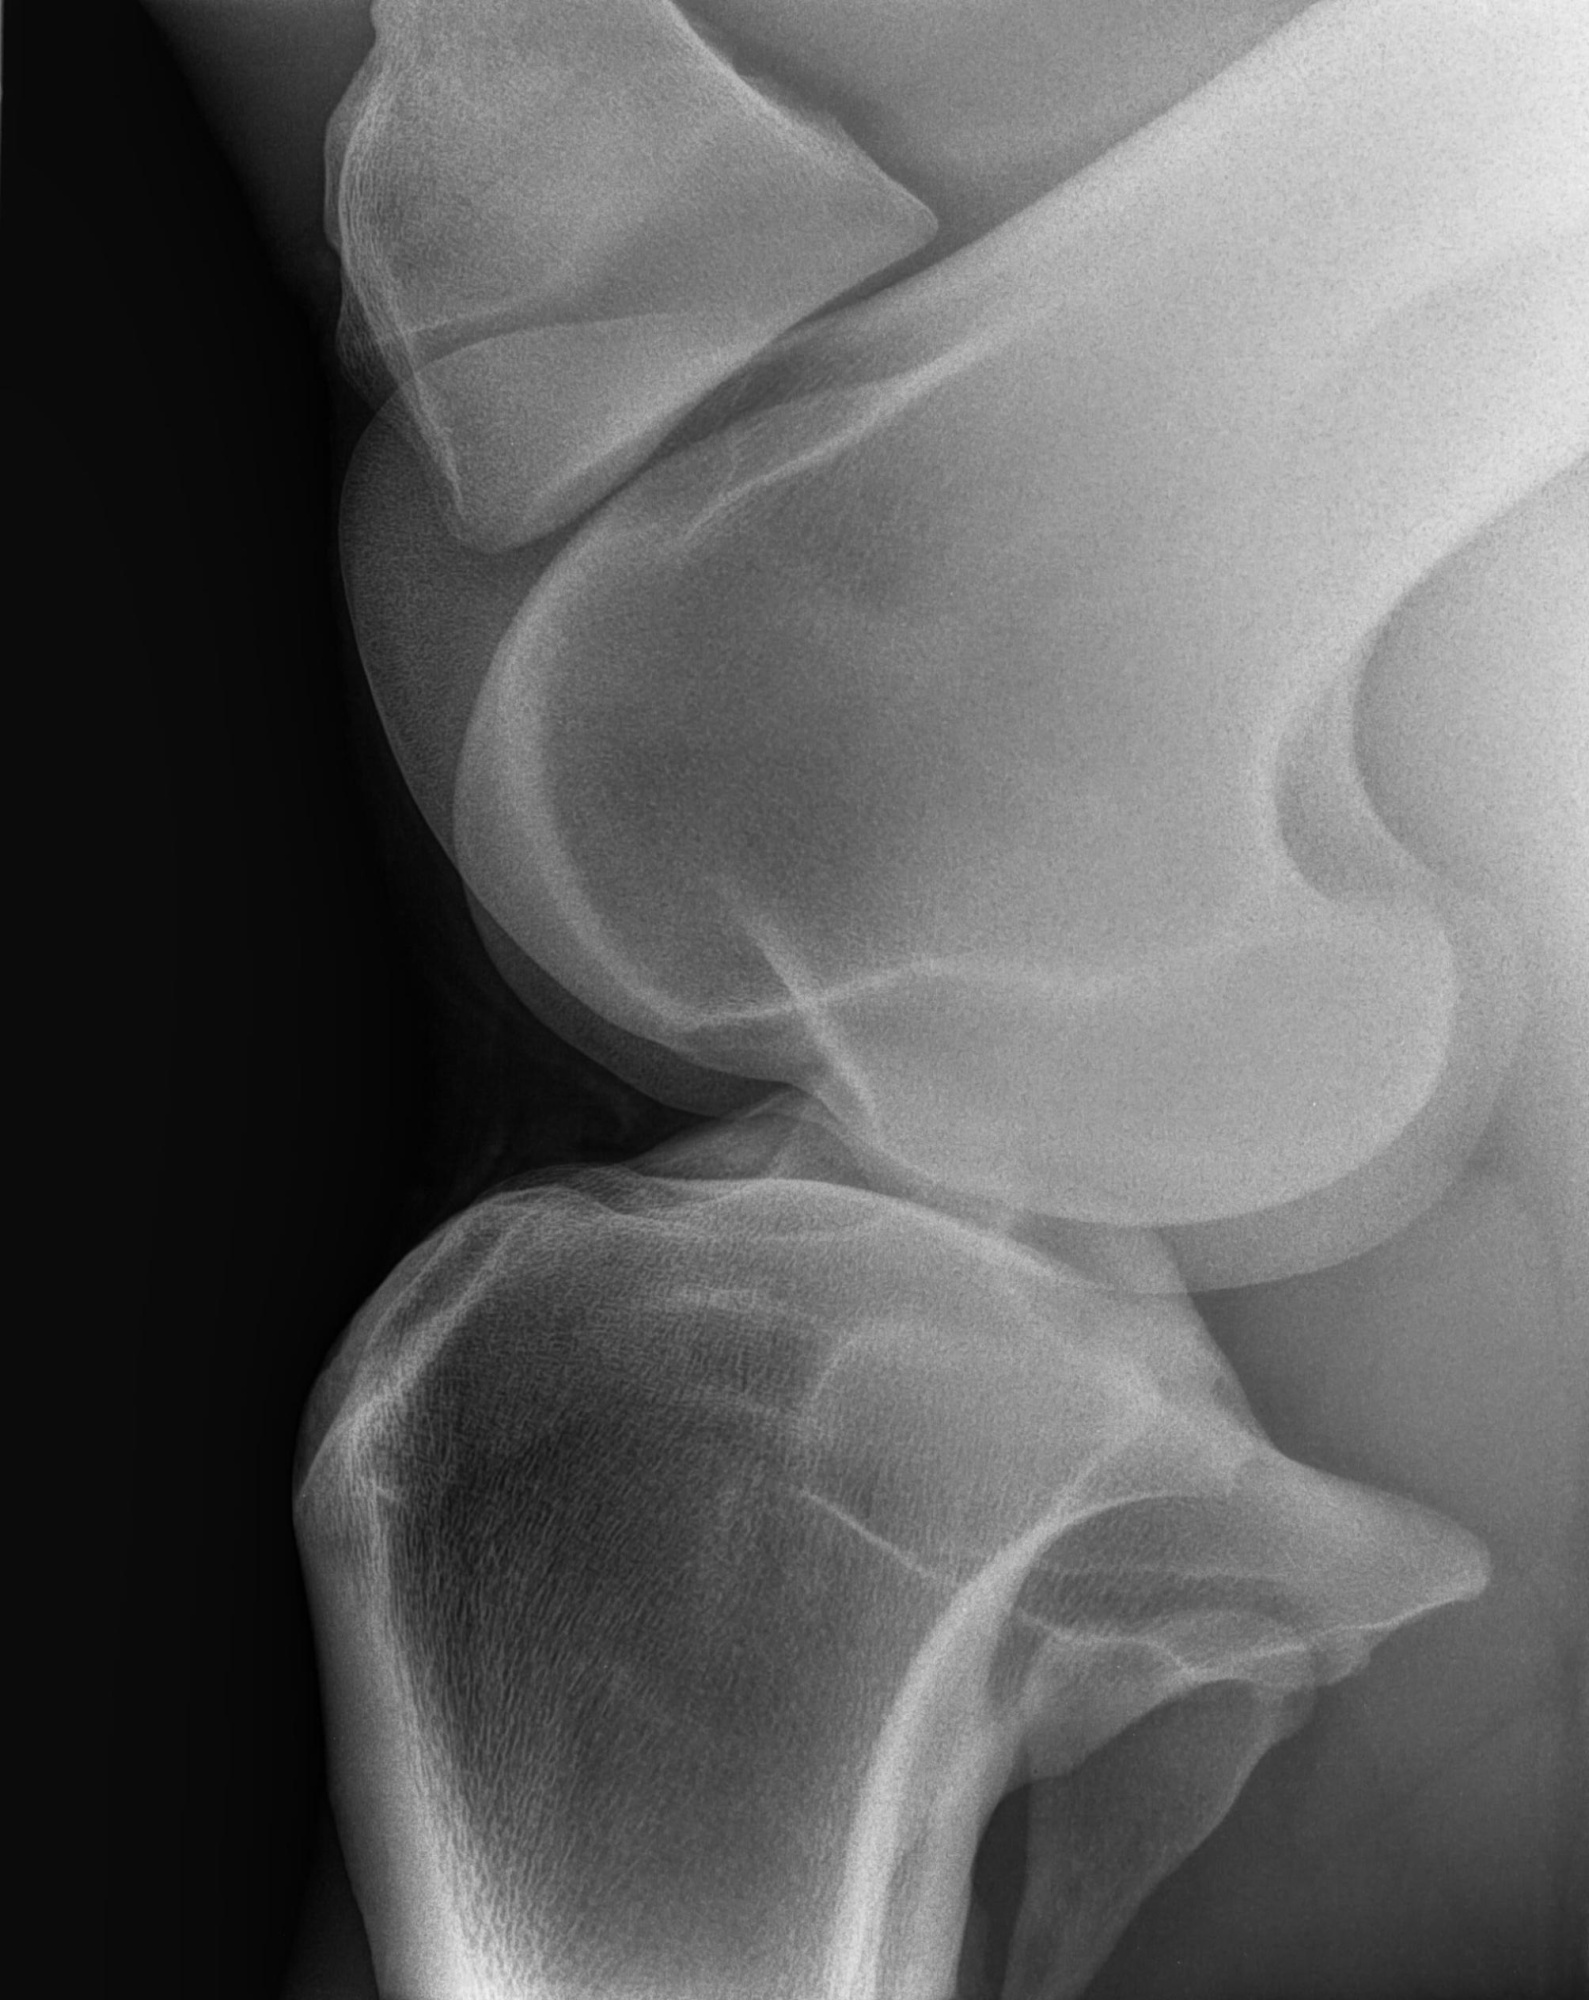

«Довольны на все 100%» – заявил клиент. – «Работать с DR-панелью через программу быстро и не сложно. Рентген «видит» крупных животных, иногда берём его на выезды.»